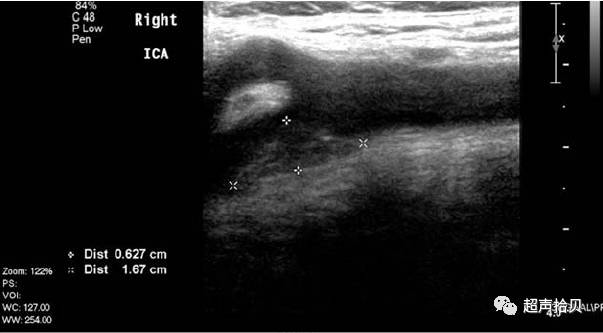

图4.女,41岁,左侧颈部疼痛。 A,颈动脉病变位于右前方 B,用非甾体抗炎治疗后消失;CCA颈总动脉。